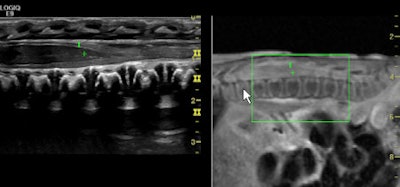

Side-by-side fusion imaging of real-time high-frequency ultrasound and MR images show the pediatric spine in a neonate with meningitis. Image courtesy of GE Healthcare.Concerned that ordering musculoskeletal ultrasonography is often based on the experience of a referring physician or sonographer, the European Society of Musculoskeletal Radiology (ESSR) selected a panel of experts from Austria, Belgium, Denmark, France, Italy, the Netherlands, and the U.K. in 2008 to work on the guidelines. Recommendations were based on the clinical condition, its level of evidence, the strength of the recommendations, and the percentage of agreement. Each clinical indication was then given an appropriateness grade, from zero (ultrasound not indicated) to three (ultrasound = first exam choice).